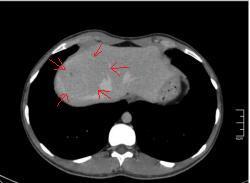

КТ печени. Наблюдения для размышления.

Уважаемые коллеги, особенно врачи КТ. Надеюсь что данная публикация окажется полезной для многих из Вас. Ниже представлены сканы печени; предлагаю Вам ознакомится с ними и высказать свое мнение. Пациент мужчина средних лет, специфичных жалоб не предъявляет.

Если Вы не против, я немного придержу продолжение данного наблюдения. Основная задача данной публикации не сам диагноз, а показать современные аспекты и особенности метода КТ, а также важность глубины и объёма знаний врачей радиологов которые занимаются КТ диагностикой.

Nela: Браво! Есть непрямые (вторичные) признаки объёмного образования печени (анатомия, анатомия и ещё раз анатомия. )

Уважаемый v1tal! Огромная Вам благодарность; Вы назвали ключевое слово: фаза! Высказанная Вами мысль, это моя основная цель данной публикации. Постараюсь позже более детально объяснить почему. Представленные сканы выше, были выполнены на стандартной портальное фазе. А сейчас, я покажу сканы данного пациента выполненные на артериальной фазе :

Да Ola la, Вы абсолютно правы; это Фокальная Нодулярная Гиперплазия печени (FNH Focal Nodular Hyperplasia). Одна из немногих гиперваскулярных опухолей печени. Наверное некоторые коллеги спросят, и зачем было изначально публиковать портальную фазу, на которой «не видно» (хотя опухоль видна, пусть и не напрямую, и Nela это доказала); и только потом показывать сканы на артериальной фазе, на которой всё «красиво и показательно». Постараюсь объяснить.

За эти два года, в течении которых я познакомился с радиологическим русскоговорящим интернетом, я пришёл к определённым выводам. К сожалению, при наличии уже довольно неплохого парка современной аппаратуры в клиниках России и СНГ (у меня лично аппаратура намного скромнее по возможностям чем например у Nela или v1tal), ощущается огромный пробел в знаниях очень многих врачей, которые работают на этих аппаратах. И как следствие, врачи классические рентгенологи, отправляя пациентов на до-обследование в эти клиники, получая при этом неудовлетворительный результат проведённых исследований, начинают полагать (и имеют на это право), что зачем все эти «КТ и МРТ», если мы по своим стандартным рентгенологическим методикам получаем тот же результат (если иногда и не лучше-живой пример тому публикация vital с дивертикулом пищевода, где врач КТ написал диафрагмальную грыжу). И когда я читаю такие посты, мне становится очень обидно, хотя повторюсь, я уже пониманию причины такого мышления. Тем более что мало кто знает, что КТ и МРТ это не «статические методики», при которых взял пациента, положил на стол, дал контраст (как, куда, на какой скорости-мало кого волнует), сделал одну спираль/фазу, и до свиданья, «подавайте» следующего. Современные протоколы КТ и МРТ выработаны ПОД КАЖДЫЙ КОНКРЕТНЫЙ ДИАГНОЗ, иными словами, если мы подозреваем заболевание кишечника, и снимем пациента по протоколу разработанному для диагностики патологии печени или поджелудочной, то мы можем пропустить «всё на свете» в кишечнике, и при этом ничего не найти в печени или панкреас.